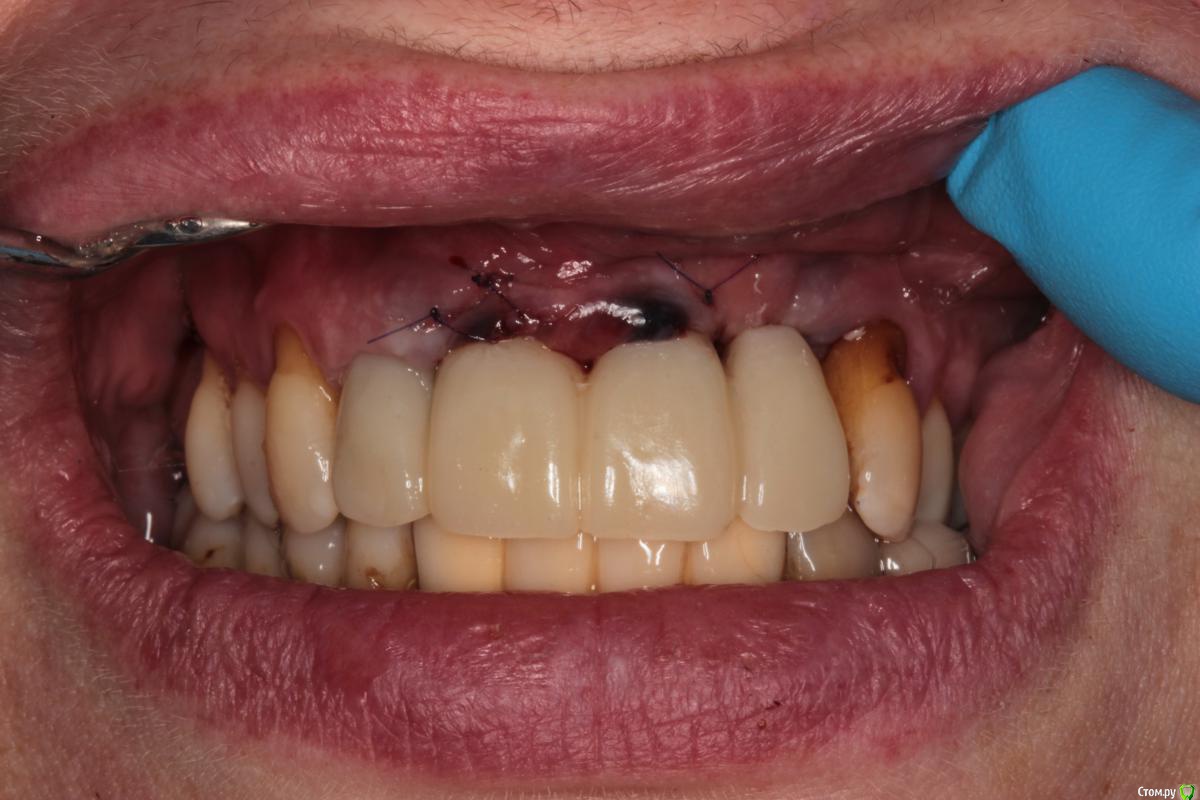

Abuk Опубликовано 27 ноября, 2015 Поделиться Опубликовано 27 ноября, 2015 (изменено) 1.bmp2.bmp3.bmp4.bmpЛечение.Альгинатные слепки,восковая моделировка.Удаление зубов и имплантата,удаление грануляций.Установка имплантатов,заполнение лунок графтом.сст,Времяхи по ключу. Изменено 27 ноября, 2015 пользователем Abuk 13 Ссылка на комментарий

Abuk Опубликовано 29 ноября, 2015 Автор Поделиться Опубликовано 29 ноября, 2015 (изменено) 1 е фото -"до", после были слепки и гигиена.Непосредственно перед имплантацией нет.Гигиена не фонтан,условились на том что первый год приходит каждые 3 месяца(осмотр и ггигиена),а там далее смотрим. Изменено 29 ноября, 2015 пользователем Abuk Ссылка на комментарий